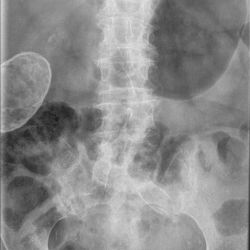

Porzellangallenblase